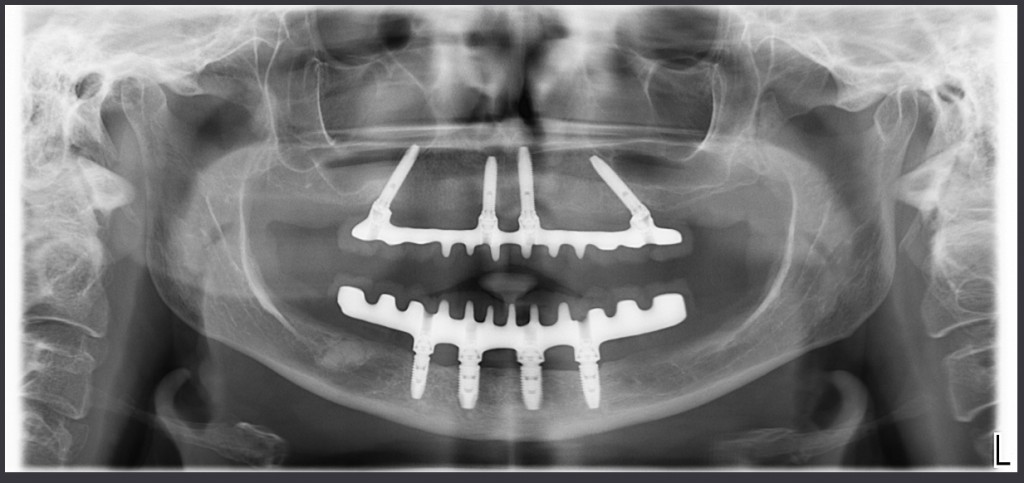

Eppure l’osso non c’era!!!! O almeno così aveva detto l’interpretazione rigida della simulazione al computer.

Questo è il controllo a un anno della mia paziente, un giorno ti mostrerò l’inferiore!